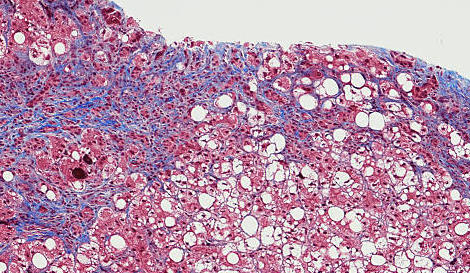

Carcinome